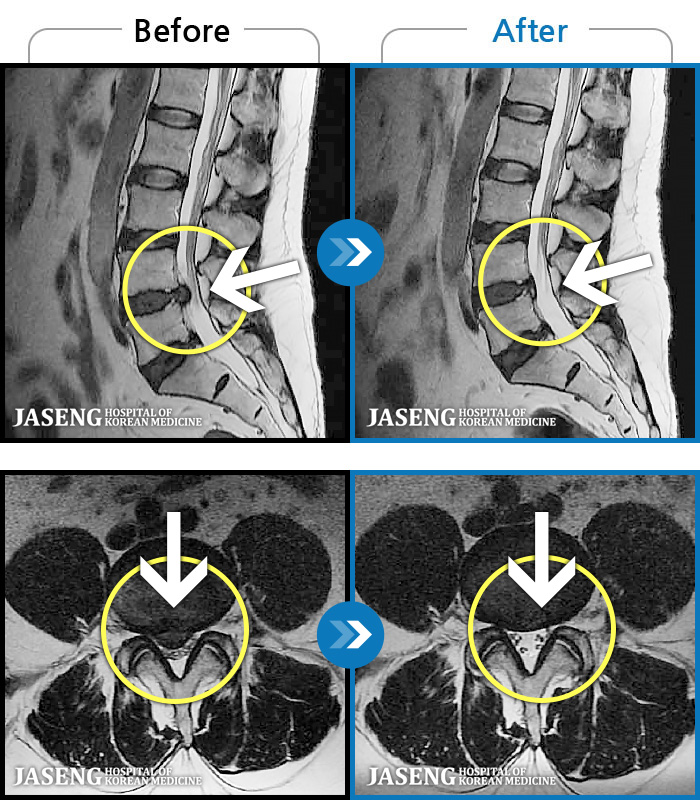

MRI ġ

1,237 MRI ũ ʸ Ȯϼ.

[Կñ:24.07.25~25.08.01]

[ϻ_㸮ũ] ݺ ӵǸ ڼ ÿ ȭǴ ߵ ̻ ȣϴ ¿ϴ.

No.1234

ȸ 253

2025.09.05